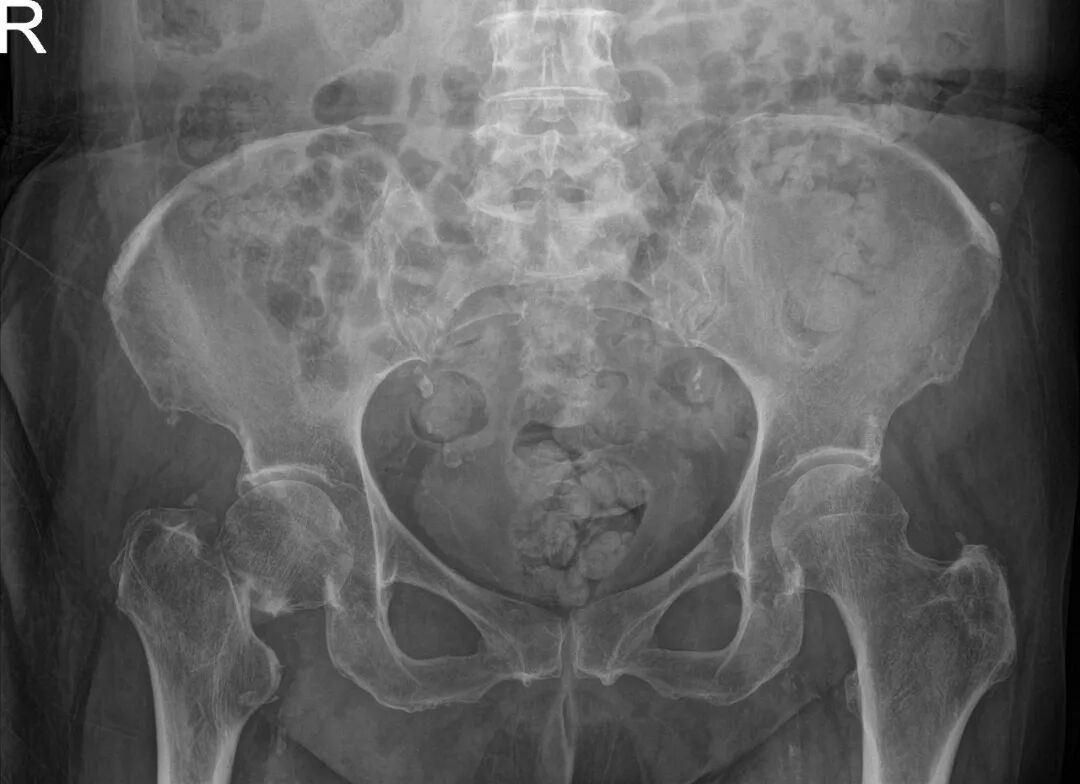

春节期间,谢阿姨因意外跌倒导致股骨颈骨折,合并有多年的慢性肾衰竭,需要长期规律透析治疗,同时高血压、2型糖尿病、冠心病等等疾病缠身,这使得她的病情变得异常复杂,患者家属带着希望辗转于各家医院却屡遭婉拒。

就在失望和无助中,患者家属慕名找到了同济医院运动医学科王家骐,他在详细了解患者病情后,深知这台手术的复杂性与高风险:股骨颈骨折对于高龄患者本就凶险,而肾衰竭更是雪上加霜——手术耐受性差、麻醉风险高、术后感染及伤口愈合困难、水电解质紊乱等问题层层叠加,极大增加了手术风险。但若不及时手术,患者将长期卧床,肺部感染、深静脉血栓、压疮等并发症随时可能危及生命。

入院后患者肾功能数次报出危急值,血肌酐高达1010μmol/L(正常值约44-133μmol/L),超出正常上限近8倍,体内毒素蓄积,水电解质严重紊乱,随时可能引发心衰、肺水肿或猝死。肾脏内科团队第一时间介入,为患者制定了个体化的透析方案,即时调整透析频率与剂量,在术前将患者内环境调整至最佳状态,为手术创造时机。王家骐综合评估患者病情,把握两次透析间期中的手术黄金窗口期,为患者施行手术治疗。

手术当日,在麻醉科执行主任刘建慧和手术室护士长姚英的支持下,麻醉团队、器械护士与巡回护士紧密配合,为手术保驾护航。王家骐亲自主刀,带领运动医学科手术团队,凭借丰富的临床经验与娴熟的手术技巧,为谢阿姨成功实施人工股骨头置换术。术中,团队操作精准、配合默契,从切开到假体安装一气呵成,最大限度缩短手术时间,减少手术创伤,为术后快速康复奠定基础。